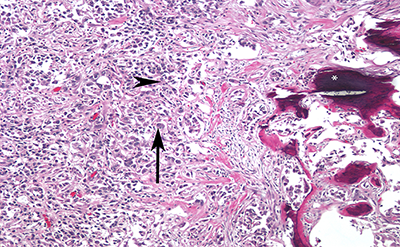

On gross pathologic analysis, a

yellow-tan, circumscribed and lobulated mass measuring 4.2 x 3.5 x 2.7 cm was

found in the cortico-medullary junction of the upper pole. A pale tan tumor thrombus was identified in

the renal pelvis, while no thrombus was identified in the renal vein. On microscopic examination, focal necrosis

and multiple foci of osseous metaplasia were noted (Figure 2). On

immunohistochemistry, tumor cells were positive for PAX8, focally positive for

CA-IX, and largely negative for CK903, p63, and GATA3. These findings are consistent with collecting

duct carcinoma with sarcomatoid differentiation. The tumor was found to be invading the renal

pelvis, renal cortex and perinephric fat; the sinus fat and renal vasculature

were uninvolved. Thirty-five lymph nodes

were removed, and seven were found to contain metastatic cancer.

Figure 2. High

magnification photomicrograph showing highly infiltrative carcinoma with

tubular structure, embedded in desmoplastic stroma. The tumor cells have eosinophilic cytoplasm

(arrowhead), the nuclei are large and pleomorphic, with prominent nucleoli

(arrow) and coarse chromatin. Also seen

is evidence of ossification (*).